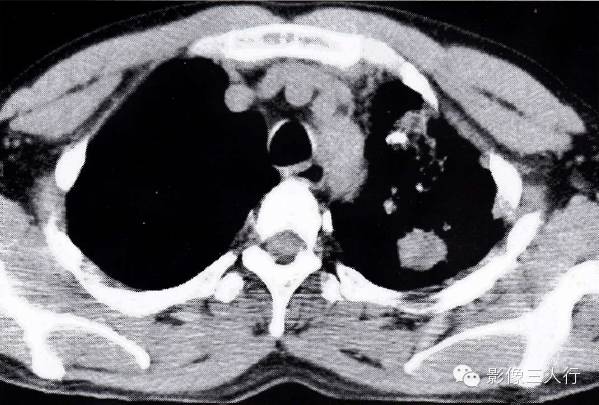

图2-94肺结核合并肺癌

左肺下叶肺结核,斑状影,条索状影,内有结节影,肺穿刺为腺癌 在肺不张时见支气管阻塞,肺门区出现肿块而且肺门区出现支气管腔内外融合成一体的肿块,腔内与腔外部分呈一致性强化。肺不张内无明显空洞及扩张的支气管影。